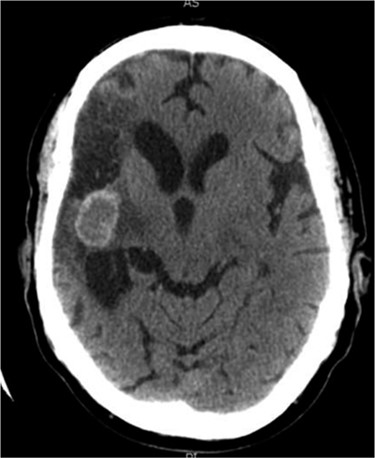

At follow-up it was noted that the patient was experiencing headaches, had poor short-term memory and decreased sensation to the left side of his body. The hemiparesis persisted and a left upper motor neuron facial palsy was noted. In 2005 and in light of persisting symptoms, a follow-up CT scan was reported to show a small, hyper-dense cystic abnormality in the right external capsule (Fig. 1). It was postulated that the lesion was probably a calcified encysted haematoma, and the symptoms were attributed to post-stroke pain.

Axial CT head (2005) demonstrating hyper-dense cystic abnormality in the right external capsule.